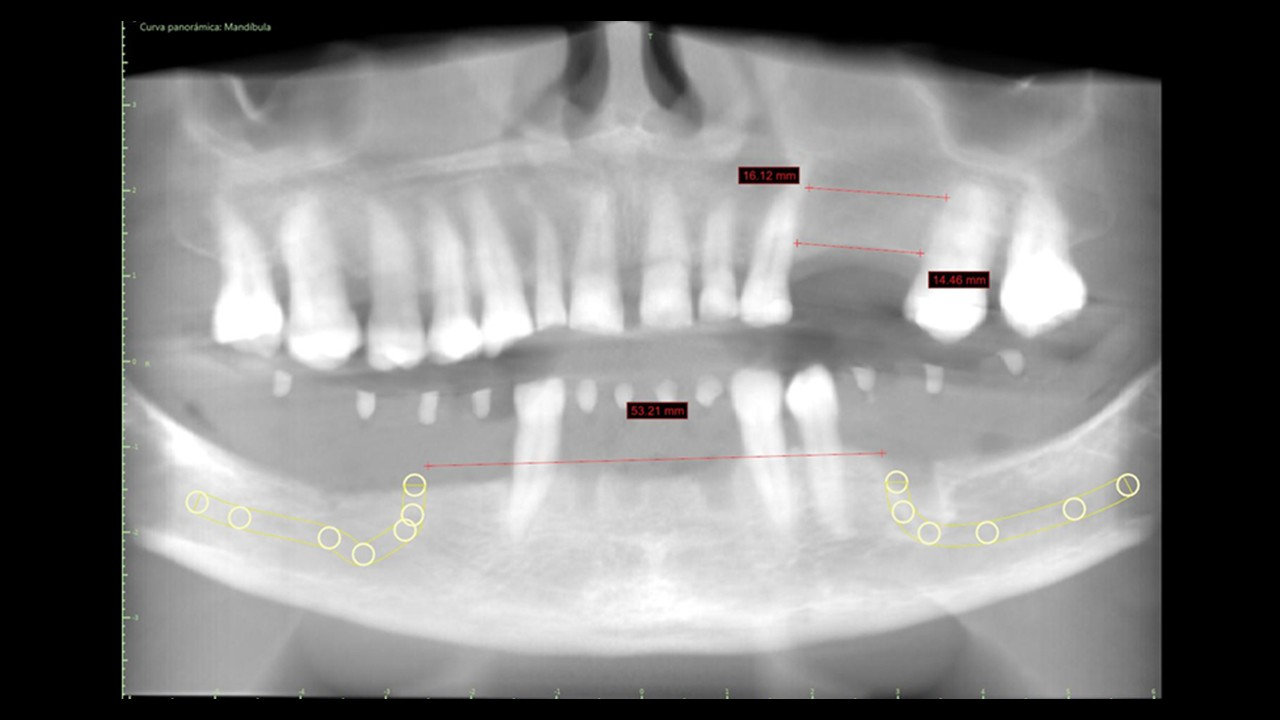

Técnica:

• Exodoncia dientes 4.3, 3.3 y 3.4.

• Colgajo espesor total en grupo V.

• Instalación de guía CX para desgaste de reborde óseo.

• Instalación de guía CX para posicionamiento de IOI (posiciones 4.5, 4.3, 4.1, 3.3, 3.5).

• Regeneración ósea guiada en relación a reborde óseo y alveolos de exodoncias. Cierre con membrana colágeno.

• Prueba de estabilidad primaria en IOI que serán cargados.

• Instalación de pilares multiunit en IOI que serán cargados. Prueba de coincidencia con pilares temporales en provisorio.

• Implantes dentales Osstem TSIII Superficie SOI Ø4.0x8.5mm (#1), Ø4.0x10mm (#5), Ø3.5x10mm (#2, #3, #4).